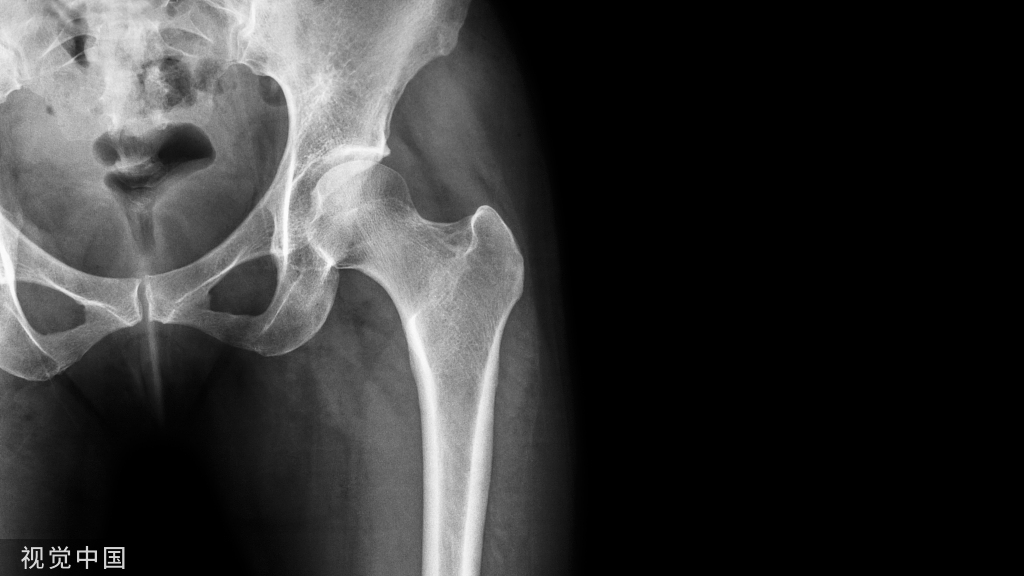

随访期间无陶瓷碎裂,5(5/85,5.9%)髋出现异响(吱吱声),3髋出现假体周围骨溶解(2髋位于股骨柄周围,Gruen分区 1和 7区,图1;1髋位于髋臼周围,DeLee -Charnley分区 2区,图2)。1例因Vancouver B2型股骨假体周围骨折而翻修(图3);1例合并系统性红斑狼疮的患者因假体周围关节感染而接受了清创术。任何原因导致再次手术的存活率为92.4%(95%置信区间为82.4%至100%)。

图2.骨溶解位于DeLee -Charnley分区 2区